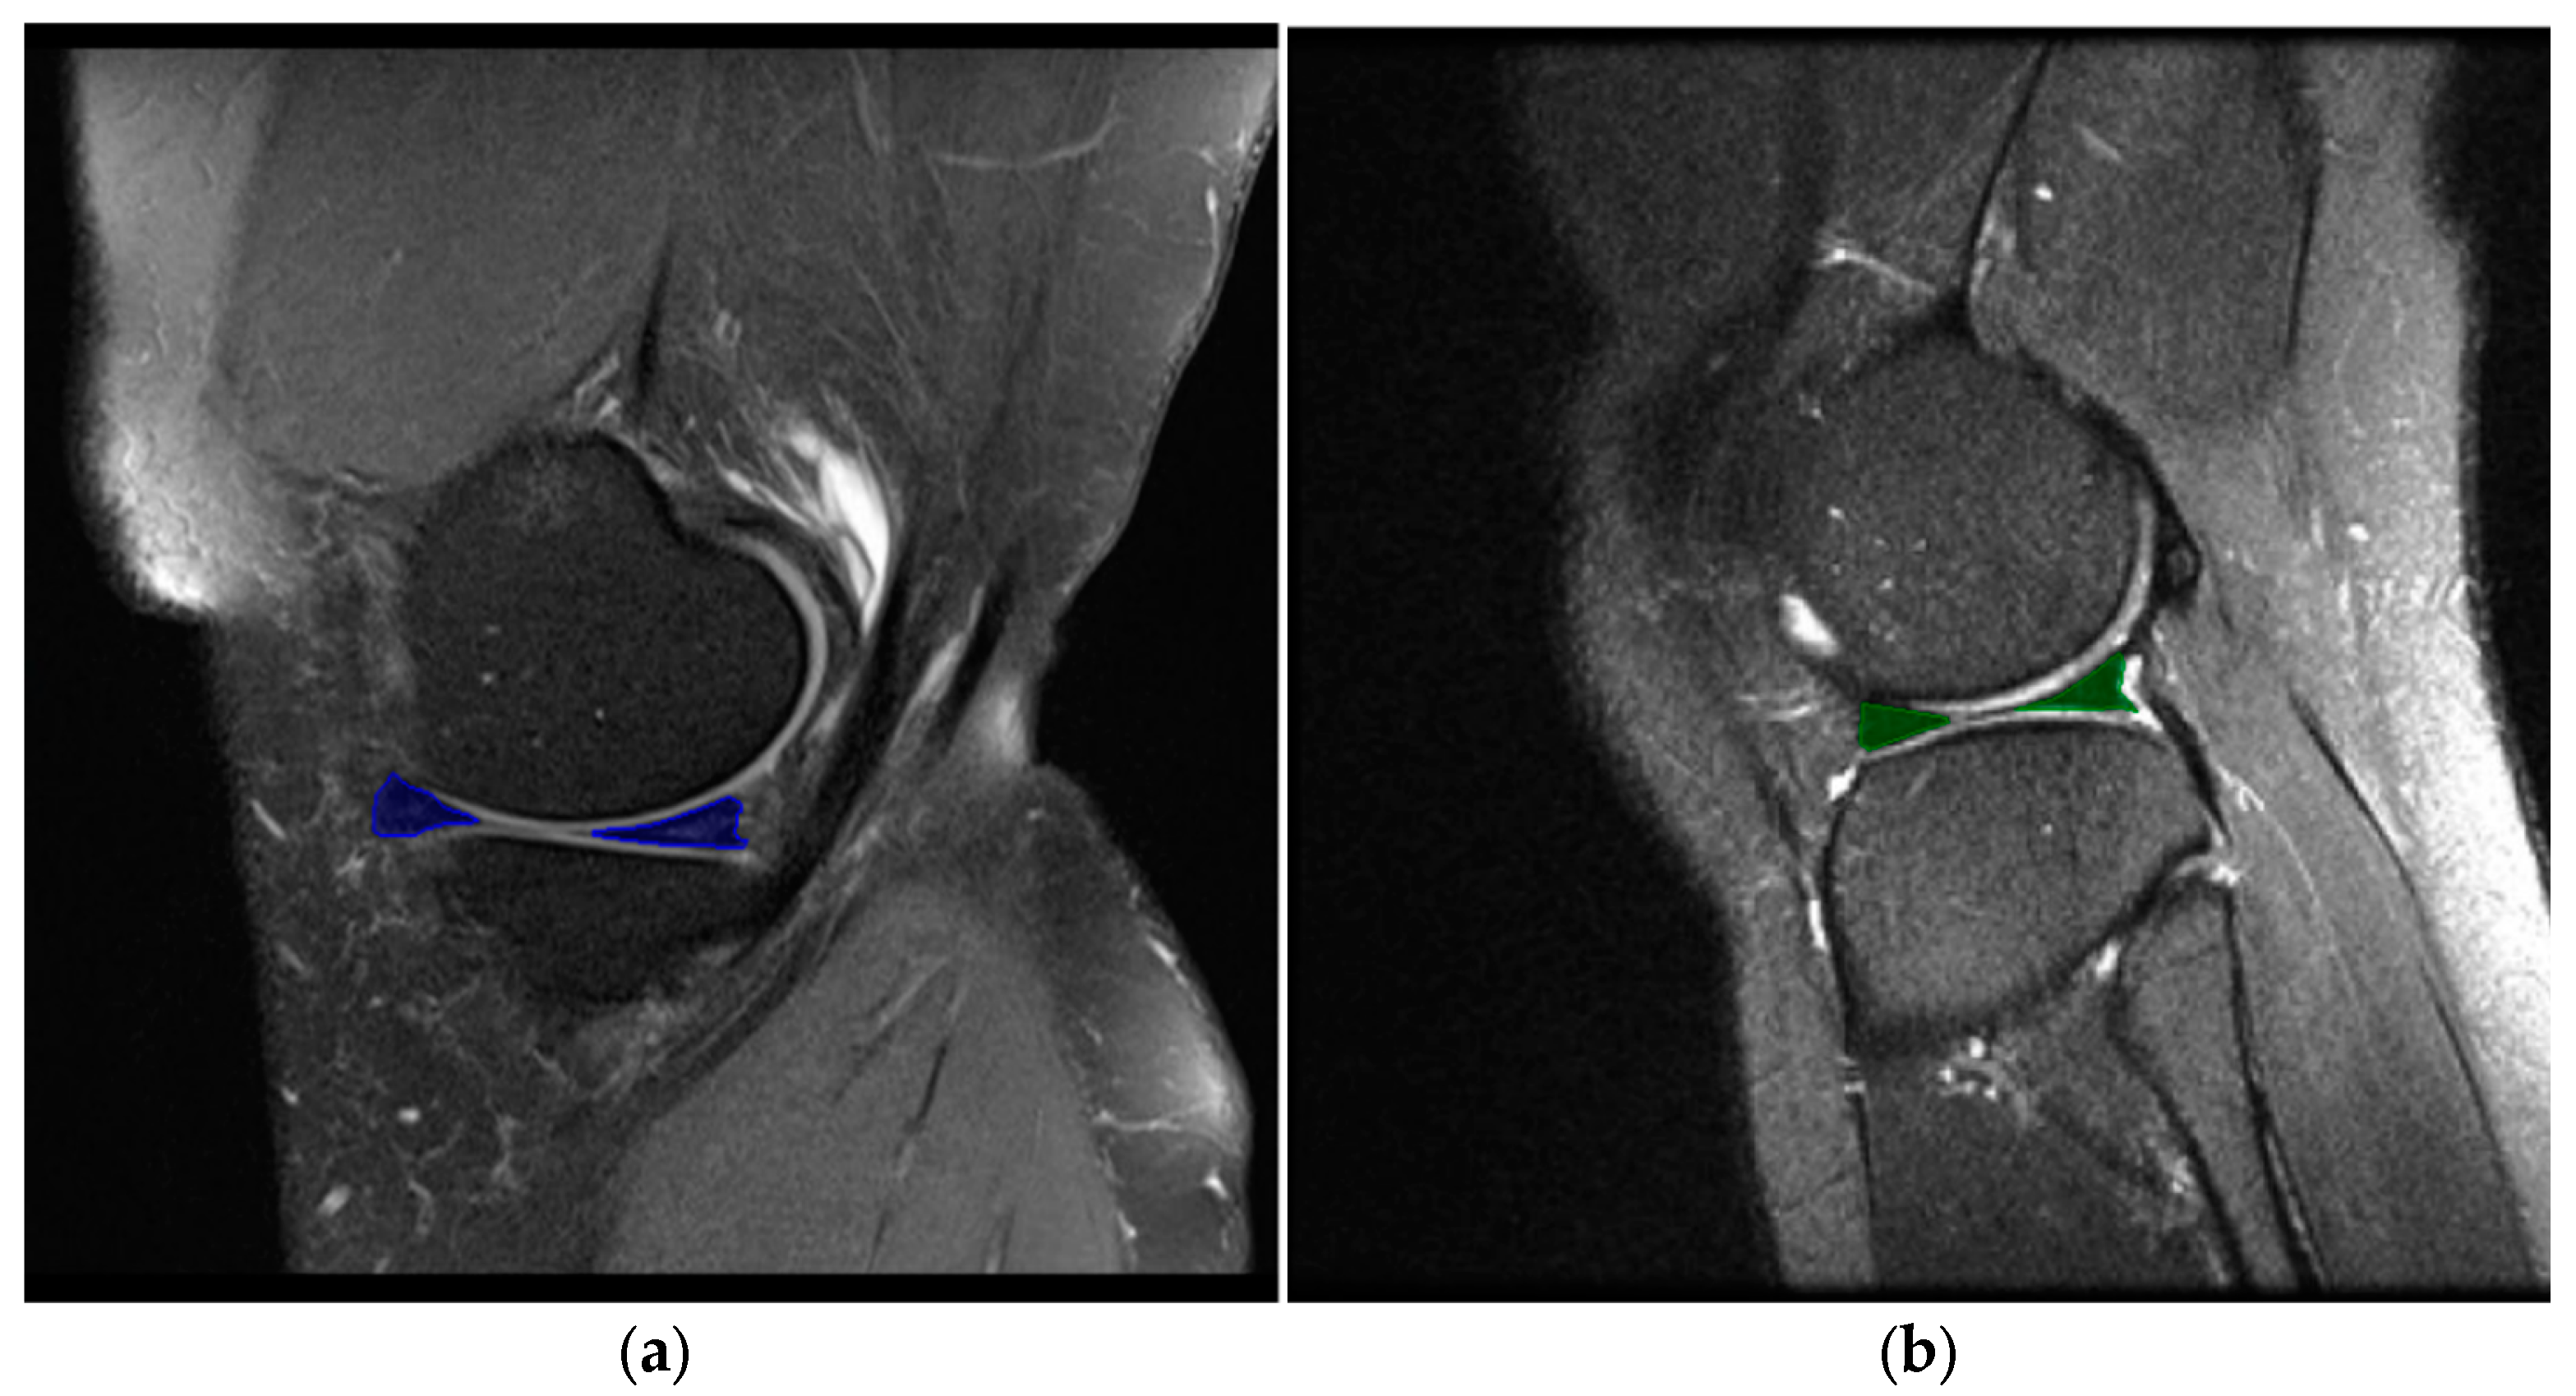

2.5. Image Selection and Labeling

In this study, image selection and labeling of the meniscal region of interest (ROI) areas were performed by a radiologist with 12 years of experience and an orthopedic and traumatologist with 12 years of experience. Considering that sagittal slices contain the most information on meniscal tears and because they better meet the clinical requirements [16,25], only sagittal slice images were used in this study. In image selection, images including both the anterior and posterior horns in the sagittal planes were preferred. Still, images showing the medial region of the meniscus were also included in the dataset. These labels produced by experienced radiologists and orthopedists were used as the gold standard (Figure 3). This study created separate ROIs for image segmentation for the anterior and posterior horn regions. A total of 1548 segmentation areas were labeled from 849 images. Of these labels, 35.70% (n = 549) belonged to the lateral meniscus (LM) and 63.30% (n = 999) to the medial meniscus (MM).

Figure 3. ROI areas for meniscal segmentation in the sagittal section. (a) An image with meniscal injury in the posterior and anterior horn of the medial meniscus in the test set. (b) Representation of healthy lateral meniscus in the external set.